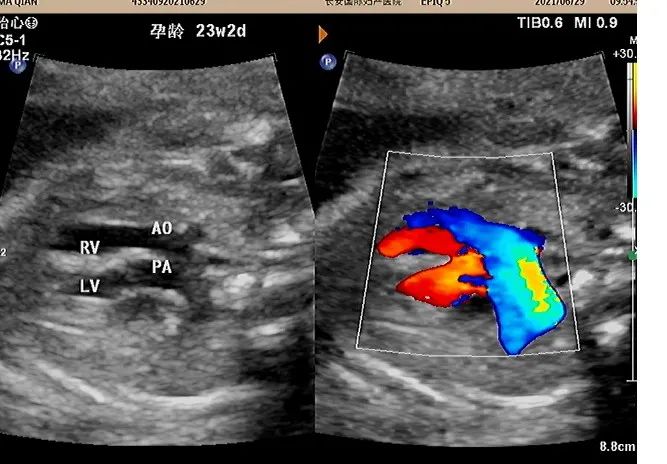

孕妇 XXX 女 28 岁 G1PO 孕 18W1D

在本院行常规筛查时发现心脏结构异常,主动脉发自与右心室,肺动脉发自于左心室,室间隔膜周部可见 3 mm 的回声中断,余结构未见异常。

为进一步评估生后手术情况,遂前往西京胎心诊断中心,诊断结论与本院一致。

完全型大动脉转位 ( TGA):即房室连接一致而心室与动脉连接不一致。心房与心室连接正常,右心房通过三尖瓣与右心室连接,左心房通过二尖瓣与左心室连接,但是大血管的连接调转肺动脉发自左心室,主动脉发自右心室。两条大动脉呈并列走行。D-TGA 可以是孤立存在的,也可伴有其他心脏异常。室间隔缺损和肺动脉狭窄 (左室流出道梗阻) 都是 D-TGA 的常见并发症,可单独存在,也可联合发病。

完全性大动脉转位也属于紫绀型心脏病,临床出现紫绀、呼吸困难能症状,所以出生后不久就需要进行大动脉调转手术。